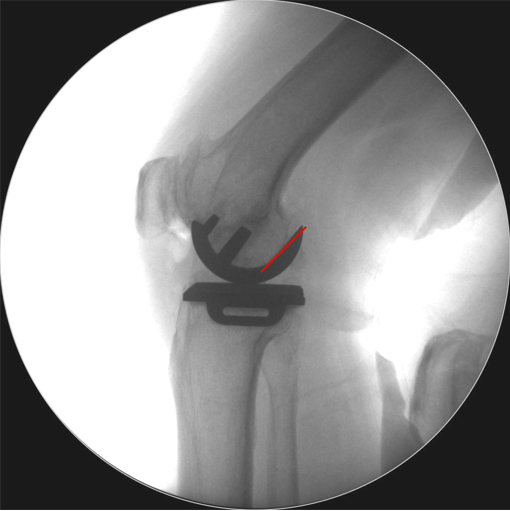

辨认bearing内的标识(透视片侧位)

bearing 内的标识:点和线段“ .—. ” 线段显示为“—”在前;点显示为“.”在后

Bearing脱位在正位片上显示股骨与胫骨假体关节面接触,侧位片显示bearing位于关节囊前方或者后方。

病例2:Bearing 破裂( X-ray侧位)

解读:股骨假体与胫骨假体间隙还存在,在图像放大4倍情况下,才依稀看到模糊的点.